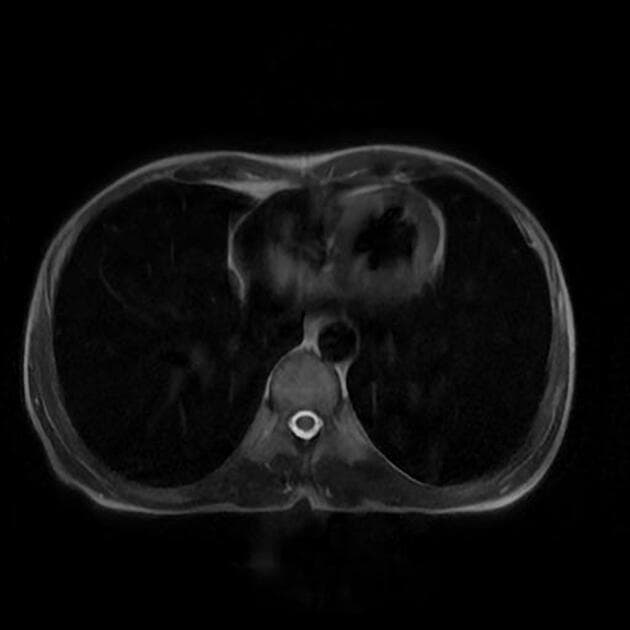

Axial T2

MRI•Axial T2•1 / 24

Ca bệnhUng thư cổ tử cung - giai đoạn IIIC1

Ung thư cổ tử cung - giai đoạn IIIC1

- Một tổn thương khối lớn quanh cổ tử cung, lan tỏa, tín hiệu trên cộng hưởng từ trọng T2 là trung gian, có hạn chế khuếch tán nước rõ rệt.

- Ung thư cổ tử cung - giai đoạn IIIC1 (cervical carcinoma - stage IIIC1)

Ung thư cổ tử cung giai đoạn IIIC1, theo hệ thống phân giai đoạn FIGO 2018, ám chỉ ung thư cổ tử cung có di căn hạch chậu được xác nhận bằng hình ảnh học hoặc giải phẫu bệnh, không có di căn xa. Giai đoạn này là điểm then chốt trong tiến triển bệnh, khi cần kết hợp kiểm soát tại chỗ với điều trị toàn thân. Dạng mô học chính trong trường hợp này là ung thư tế bào vảy, chiếm khoảng 70-80% các ca ung thư cổ tử cung, thường khởi phát từ vùng chuyển tiếp của cổ tử cung. Cộng hưởng từ (MRI) đóng vai trò quan trọng trong đánh giá giai đoạn tại chỗ, bao gồm kích thước khối u, xâm lấn tổ chức quanh cổ tử cung và hạch vùng. Hình ảnh hạn chế khuếch tán rõ rệt trên chuỗi DWI hỗ trợ chẩn đoán khối u ác tính dày đặc tế bào. Điều trị chủ yếu là hóa xạ trị đồng thời, sau đó xem xét điều trị bổ trợ tùy theo đáp ứng và tổn thương còn lại.